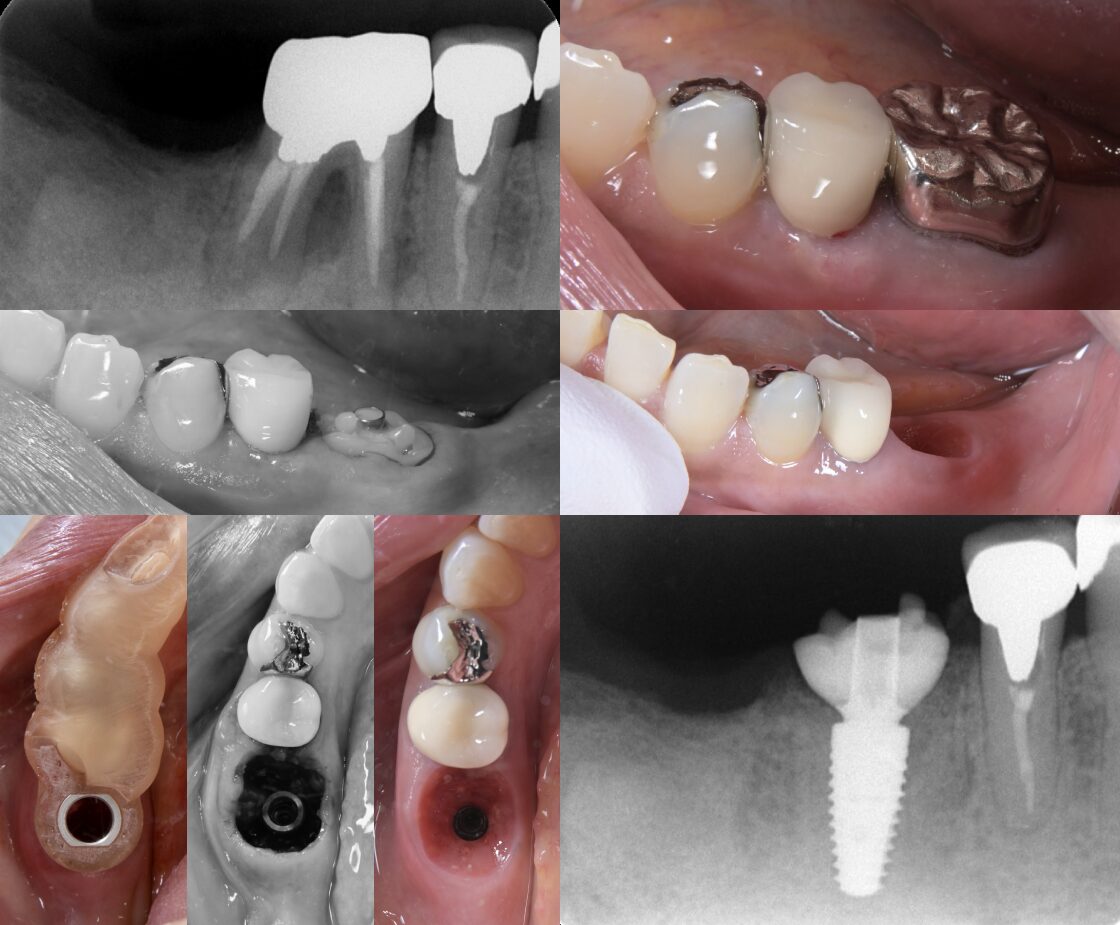

歯根破折により抜歯を要した症例への即時埋入インプラント治療

- 主訴

- 咬むと痛い

- 治療内容

- 歯根破折により保存不可能と診断し、抜歯即時埋入によるインプラント治療を行いました。

インプラント埋入前に、iOS(口腔内スキャン)データとCTデータをシミュレーションソフト上でマッチングし、埋入ポジションを決定。サージカルガイドを作製し、ガイデッドサージェリーにてインプラント手術を行いました。デジタルをインプラント治療に取り入れることで治癒期間の短縮と解剖学的形態の獲得を達成できました。また最終補綴物はジルコニアクラウンをスクリューリテイニングにて行うことでメンテナンスを容易にすることもできました。

- 治療期間

- 3ヶ月

- 治療費用

- 60万

- 治療のリスク

- 抜歯窩とインプラントとのギャップが埋入時に生じるため感染させないための処置が重要になる。またメインテナンスを容易にするためにインプラント埋入ポジションがズレないよう慎重な手技が求められる。これらを確実に行わないとインプラントが骨とうまく付かない場合があります。

BEFORE